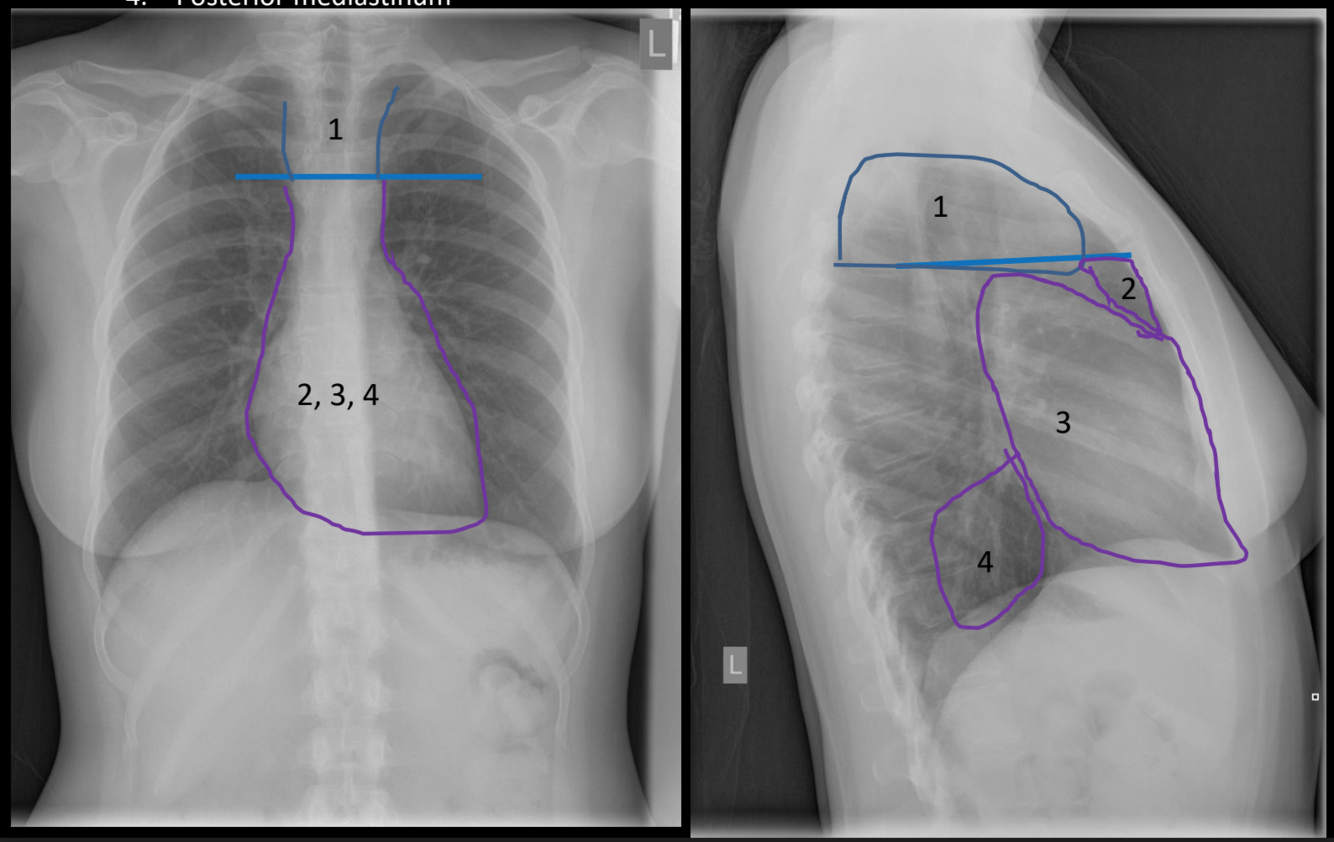

What is the space #4?

posterior mediastinum

What is the space #3?

middle mediastinum

What is the space #2?

anterior mediastinum

What is the space #1?

superior mediastinum